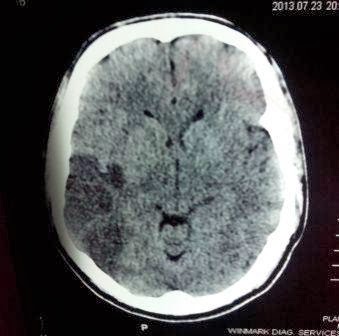

23 /7/ 13 6PM Patient

arrived at MS Bangur Institute of Neuro Sciences (a tertiary center in

Kolkata ) where a CT Scan of brain was done(See CT plate below ) was done and

for some reason the patient was referred to another center at about 11 PM .The patient moved to various hospitals and ultimately came to ED of Peerless

CT Brain taken at MS

Bangur Hospital one day ago